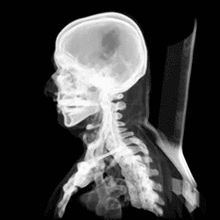

Head

CT scanning of the head is typically used to detect infarction, tumors, calcifications, haemorrhage and bone trauma. Of the above, hypodense (dark) structures can indicate edema and infarction, hyperdense (bright) structures indicate calcifications and haemorrhage and bone trauma can be seen as disjunction in bone windows. Tumors can be detected by the swelling and anatomical distortion they cause, or by surrounding edema. Ambulances equipped with small bore multi-sliced CT scanners respond to cases involving stroke or head trauma. CT scanning of the head is also used in CT-guided stereotactic surgery and radiosurgery for treatment of intracranial tumors, arteriovenous malformations and other surgically treatable conditions using a device known as the N-localizer.[12][13][14][15][16][17]

Magnetic resonance imaging (MRI) of the head provides superior information as compared to CT scans when seeking information about headache to confirm a diagnosis of neoplasm, vascular disease, posterior cranial fossa lesions, cervicomedullary lesions, or intracranial pressure disorders.[18] It also does not carry the risks of exposing the patient to ionizing radiation.[18] CT scans may be used to diagnose headache when neuroimaging is indicated and MRI is not available, or in emergency settings when hemorrhage, stroke, or traumatic brain injury are suspected.[18] Even in emergency situations, when a head injury is minor as determined by a physician's evaluation and based on established guidelines, CT of the head should be avoided for adults and delayed pending clinical observation in the emergency department for children.[19]